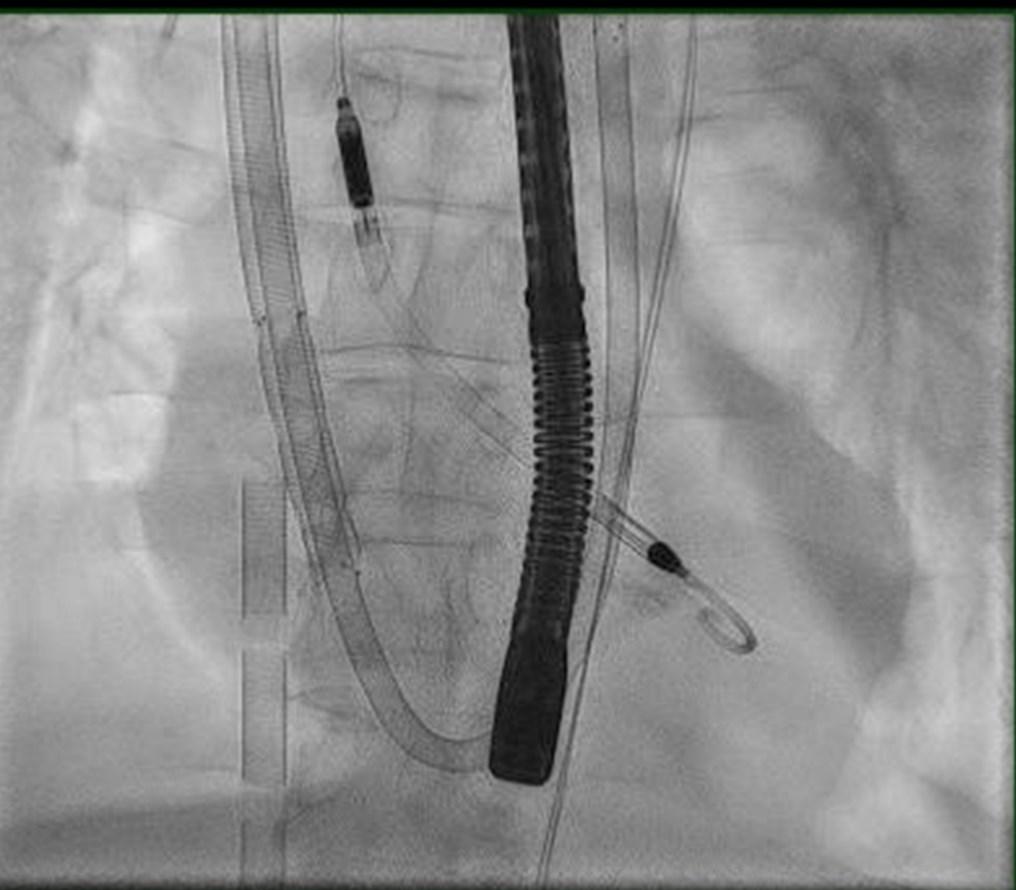

Figure 1

fluoroscopy were also utilized to ensure proper placement. Next, 5 French antegrade distal perfusion catheters were placed in bilateral superficial femoral arteries spliced from the VA ECMO circuit to provide perfusion to the lower extremities. Despite adequate mechanical flow rates, the patient developed ventricular fibrillation requiring three more defibrillation attempts prior to success. Unfortunately, the echo after this event showed complete cardiac standstill. He was transferred to the Cardiac Care Unit (CCU).

illustrates radiographic evidence of proper placement, echocardiography and Figure 1: Radiologic imaging of VA ECMO and Impella CP in place. Original Work by Study Institution

Figure 2: Fluoroscopy image of VA ECMO, ProtekDuo and Impella CP utilizing transesophageal guidance.